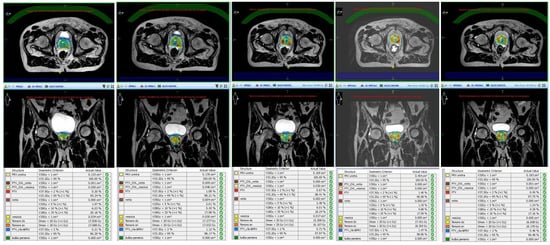

- Cuccia, F.; Mazzola, R.; Nicosia, L.; Figlia, V.; Giaj-Levra, N.; Ricchetti, F.; Rigo, M.; Vitale, C.; Mantoan, B.; De Simone, A.; et al. Impact of hydrogel peri-rectal spacer insertion on prostate gland intra-fraction motion during 1.5 T MR-guided stereotactic body radiotherapy. Radiat. Oncol. 2020, 15, 1–9. [Google Scholar] [CrossRef] [PubMed]

- Ruggieri, R.; Rigo, M.; Naccarato, S.; Gurrera, D.; Figlia, V.; Mazzola, R.; Ricchetti, F.; Nicosia, L.; Giaj-Levra, N.; Cuccia, F.; et al. Adaptive SBRT by 1.5 T MR-linac for prostate cancer: On the accuracy of dose delivery in view of the prolonged session time. Phys. Med. 2020, 80, 34–41. [Google Scholar] [CrossRef] [PubMed]

- Alongi, F.; Rigo, M.; Figlia, V.; Cuccia, F.; Giaj-Levra, N.; Nicosia, L.; Ricchetti, F.; Sicignano, G.; De Simone, A.; Naccarato, S.; et al. 1.5 T MR-guided and daily adapted SBRT for prostate cancer: Feasibility, preliminary clinical tolerability, quality of life and patient-reported outcomes during treatment. Radiat. Oncol. 2020, 15, 1–9. [Google Scholar] [CrossRef]

- Nicosia, L.; Sicignano, G.; Rigo, M.; Figlia, V.; Cuccia, F.; De Simone, A.; Giaj-Levra, N.; Mazzola, R.; Naccarato, S.; Ricchetti, F.; et al. Daily dosimetric variation between image-guided volumetric modulated arc radiotherapy and MR-guided daily adaptive radiotherapy for prostate cancer stereotactic body radiotherapy. Acta Oncol. 2021, 60, 215–221. [Google Scholar] [CrossRef] [PubMed]